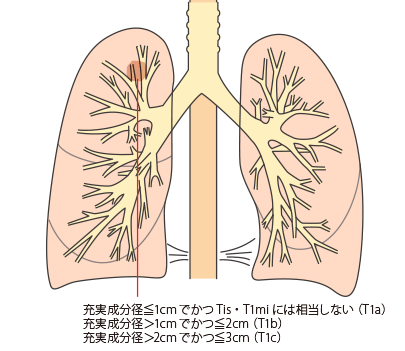

TNM分類:T‐原発巣の進展度

腫瘍の大きさ

上皮内がん(carcinoma in situ):肺野型の場合は、充実成分径0cmかつ病変全体径≦3cm

T1・T1mi

T1:腫瘍の充実成分径≦3cm、肺か臓側胸膜に覆われている、葉気管支より中枢への浸潤が気管支鏡上認められない(すなわち主気管支に及んでいない)

T1mi:微小浸潤性腺がん:部分充実型を示し、充実成分径≦0.5cmかつ病変全体径≦3cm

T1a・T1b・T1c

T2

充実成分径>3cmでかつ≦5cm、または充実成分径≦3cmでも以下のいずれかであるもの

- ・主気管支に及ぶが気管分岐部には及ばない

- ・臓側胸膜に浸潤

- ・肺門まで連続する部分的または一側全体の無気肺か閉塞性肺炎がある

T2a:充実成分径>3cmでかつ≦4cm

T2b:充実成分径>4cmでかつ≦5cm